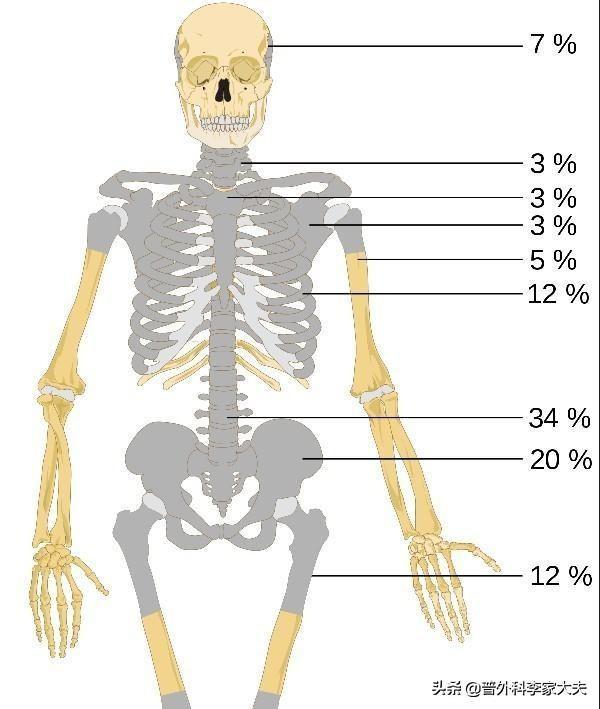

Les métastases osseuses survenant dans la colonne vertébrale sont les plus fréquentes (34 %), suivies par le bassin (20 %) et les os longs des membres inférieurs (12 %).。

Quel type de douleur doit alerter sur la présence de métastases osseuses ? Les métastases osseuses sont une manifestation fréquente des tumeurs malignes à un stade avancé. La tumeur primaire présente dans d'autres parties du corps se métastase dans les os par les voies sanguines et lymphatiques, formant ainsi des métastases osseuses. Les métastases osseuses signifient que le tissu osseux normal a été détruit et remplacé par du tissu tumoral. Les métastases osseuses peuvent être classées en trois types selon la spécificité de la lésion : le type ostéolytique, le type ostéogénique et le type mixte. Les sites courants de métastases osseuses sont l'os de la diaphyse moyenne (colonne vertébrale et bassin), les côtes et la métaphyse inférieure, l'os de la diaphyse moyenne étant le plus courant, ce qui est lié aux caractéristiques de l'apport sanguin dans cette zone. Comme le montre le cercle ci-dessous, les métastases osseuses sont multiples et la colonne vertébrale est en mauvais état.

- Les patients atteints de cancer ont des sites de métastases osseuses relativement favorables. La colonne vertébrale > le bassin > les os longs des membres inférieurs, les côtes > le crâne > les os longs des membres supérieurs.

Sites préférés des métastases osseuses du cancer